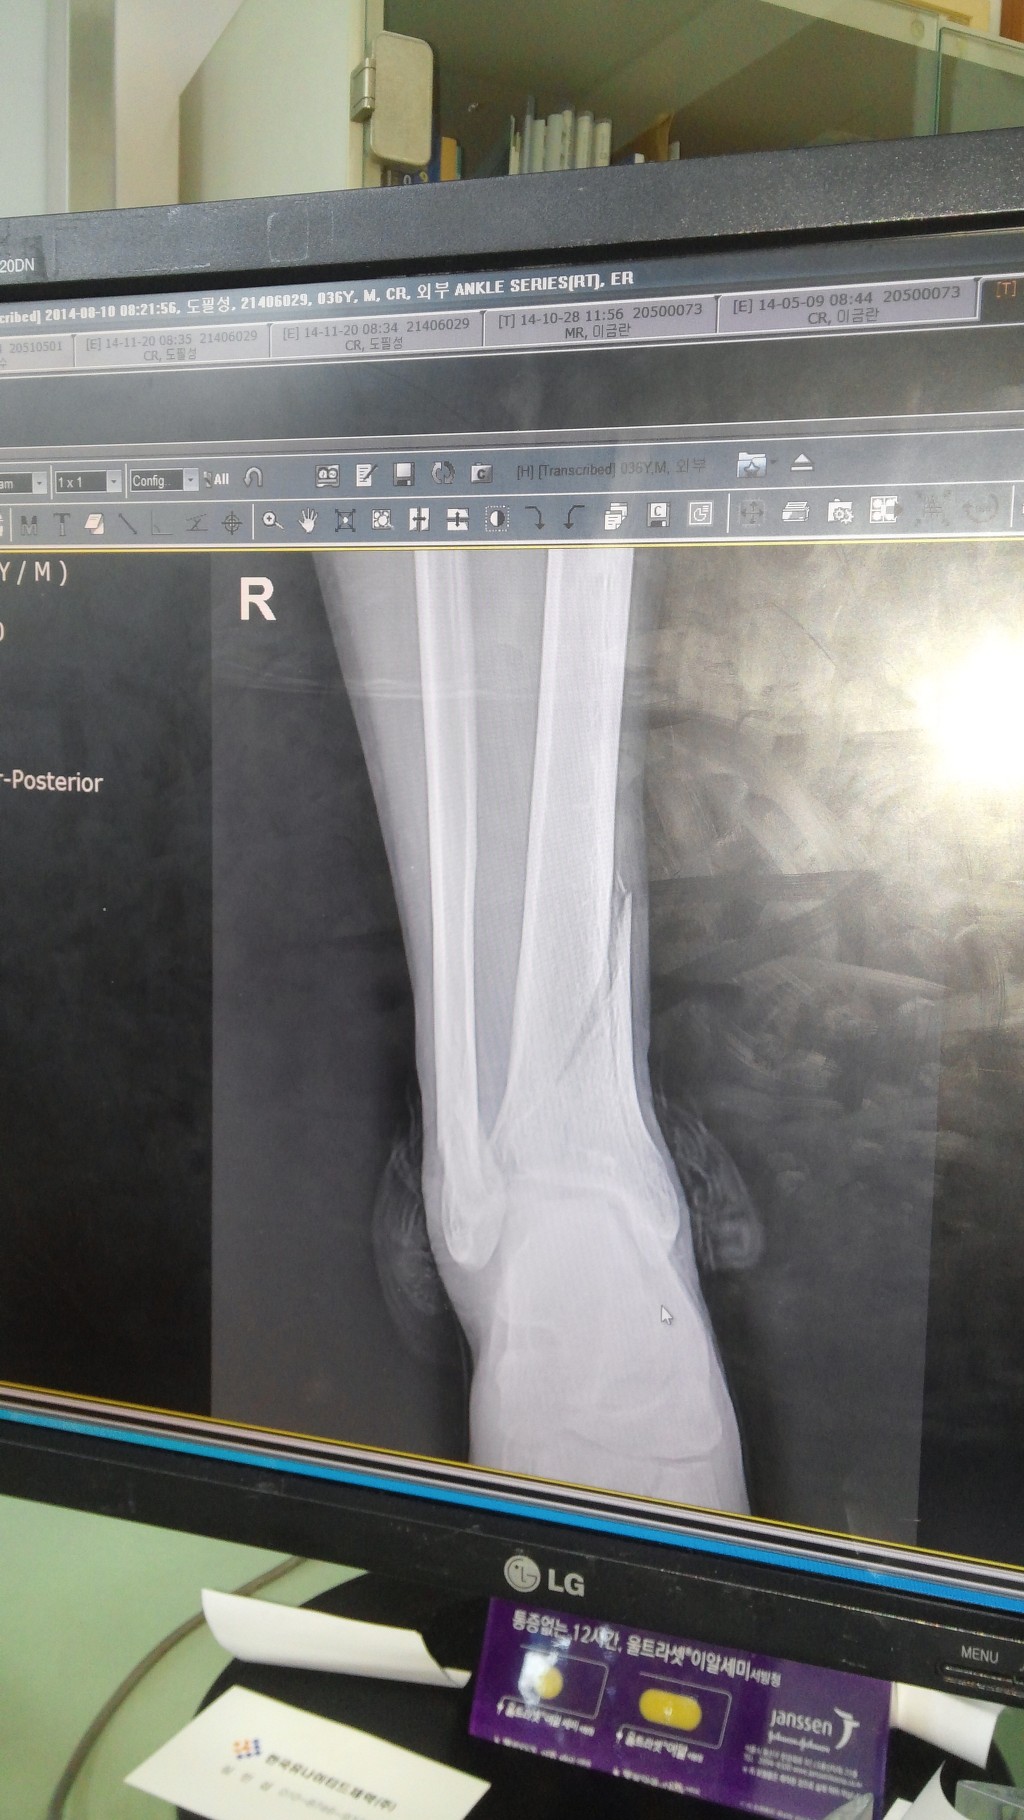

우측 족관절 원위 경골 관절내 골절, 외측과 골절, 후과 골절 수술 및 재활 과정 적습니다.15주차입니다.

8월 10일 오전 07시 평소 즐겨하던 사회인 야구를 하다가 무리한 슬라이딩으로 인한 우측 발목 위 골절이 일어났습니다. 제가 달려가는 주자였고 상대팀 포수와 그대로 충돌하였습니다.

119와서 응급실 그대로 실려갔습니다.집이 먼 관계로 응급처치만 받고 몇 시간후 와이프가 와서 집 근처 준종합병원으로 입원하였습니다.일요일이라 아무 조치도 없이 하루 보냈습니다. 물론 진통제 맞고 하였지요. 낮에는 그나마 참을만 했습니다만 밤에 자려는데 통증 정말 미치겠더군요.밤새 깨다 잠들다를 반복. 고통의 시간이였습니다. 그러다 다음날 월요일 아침. 주치의가 오셨고 붓기 때문에 바로 수술은 안되고 수요일나 금요일 하자고 하더군요. 붓기 상태보고요.